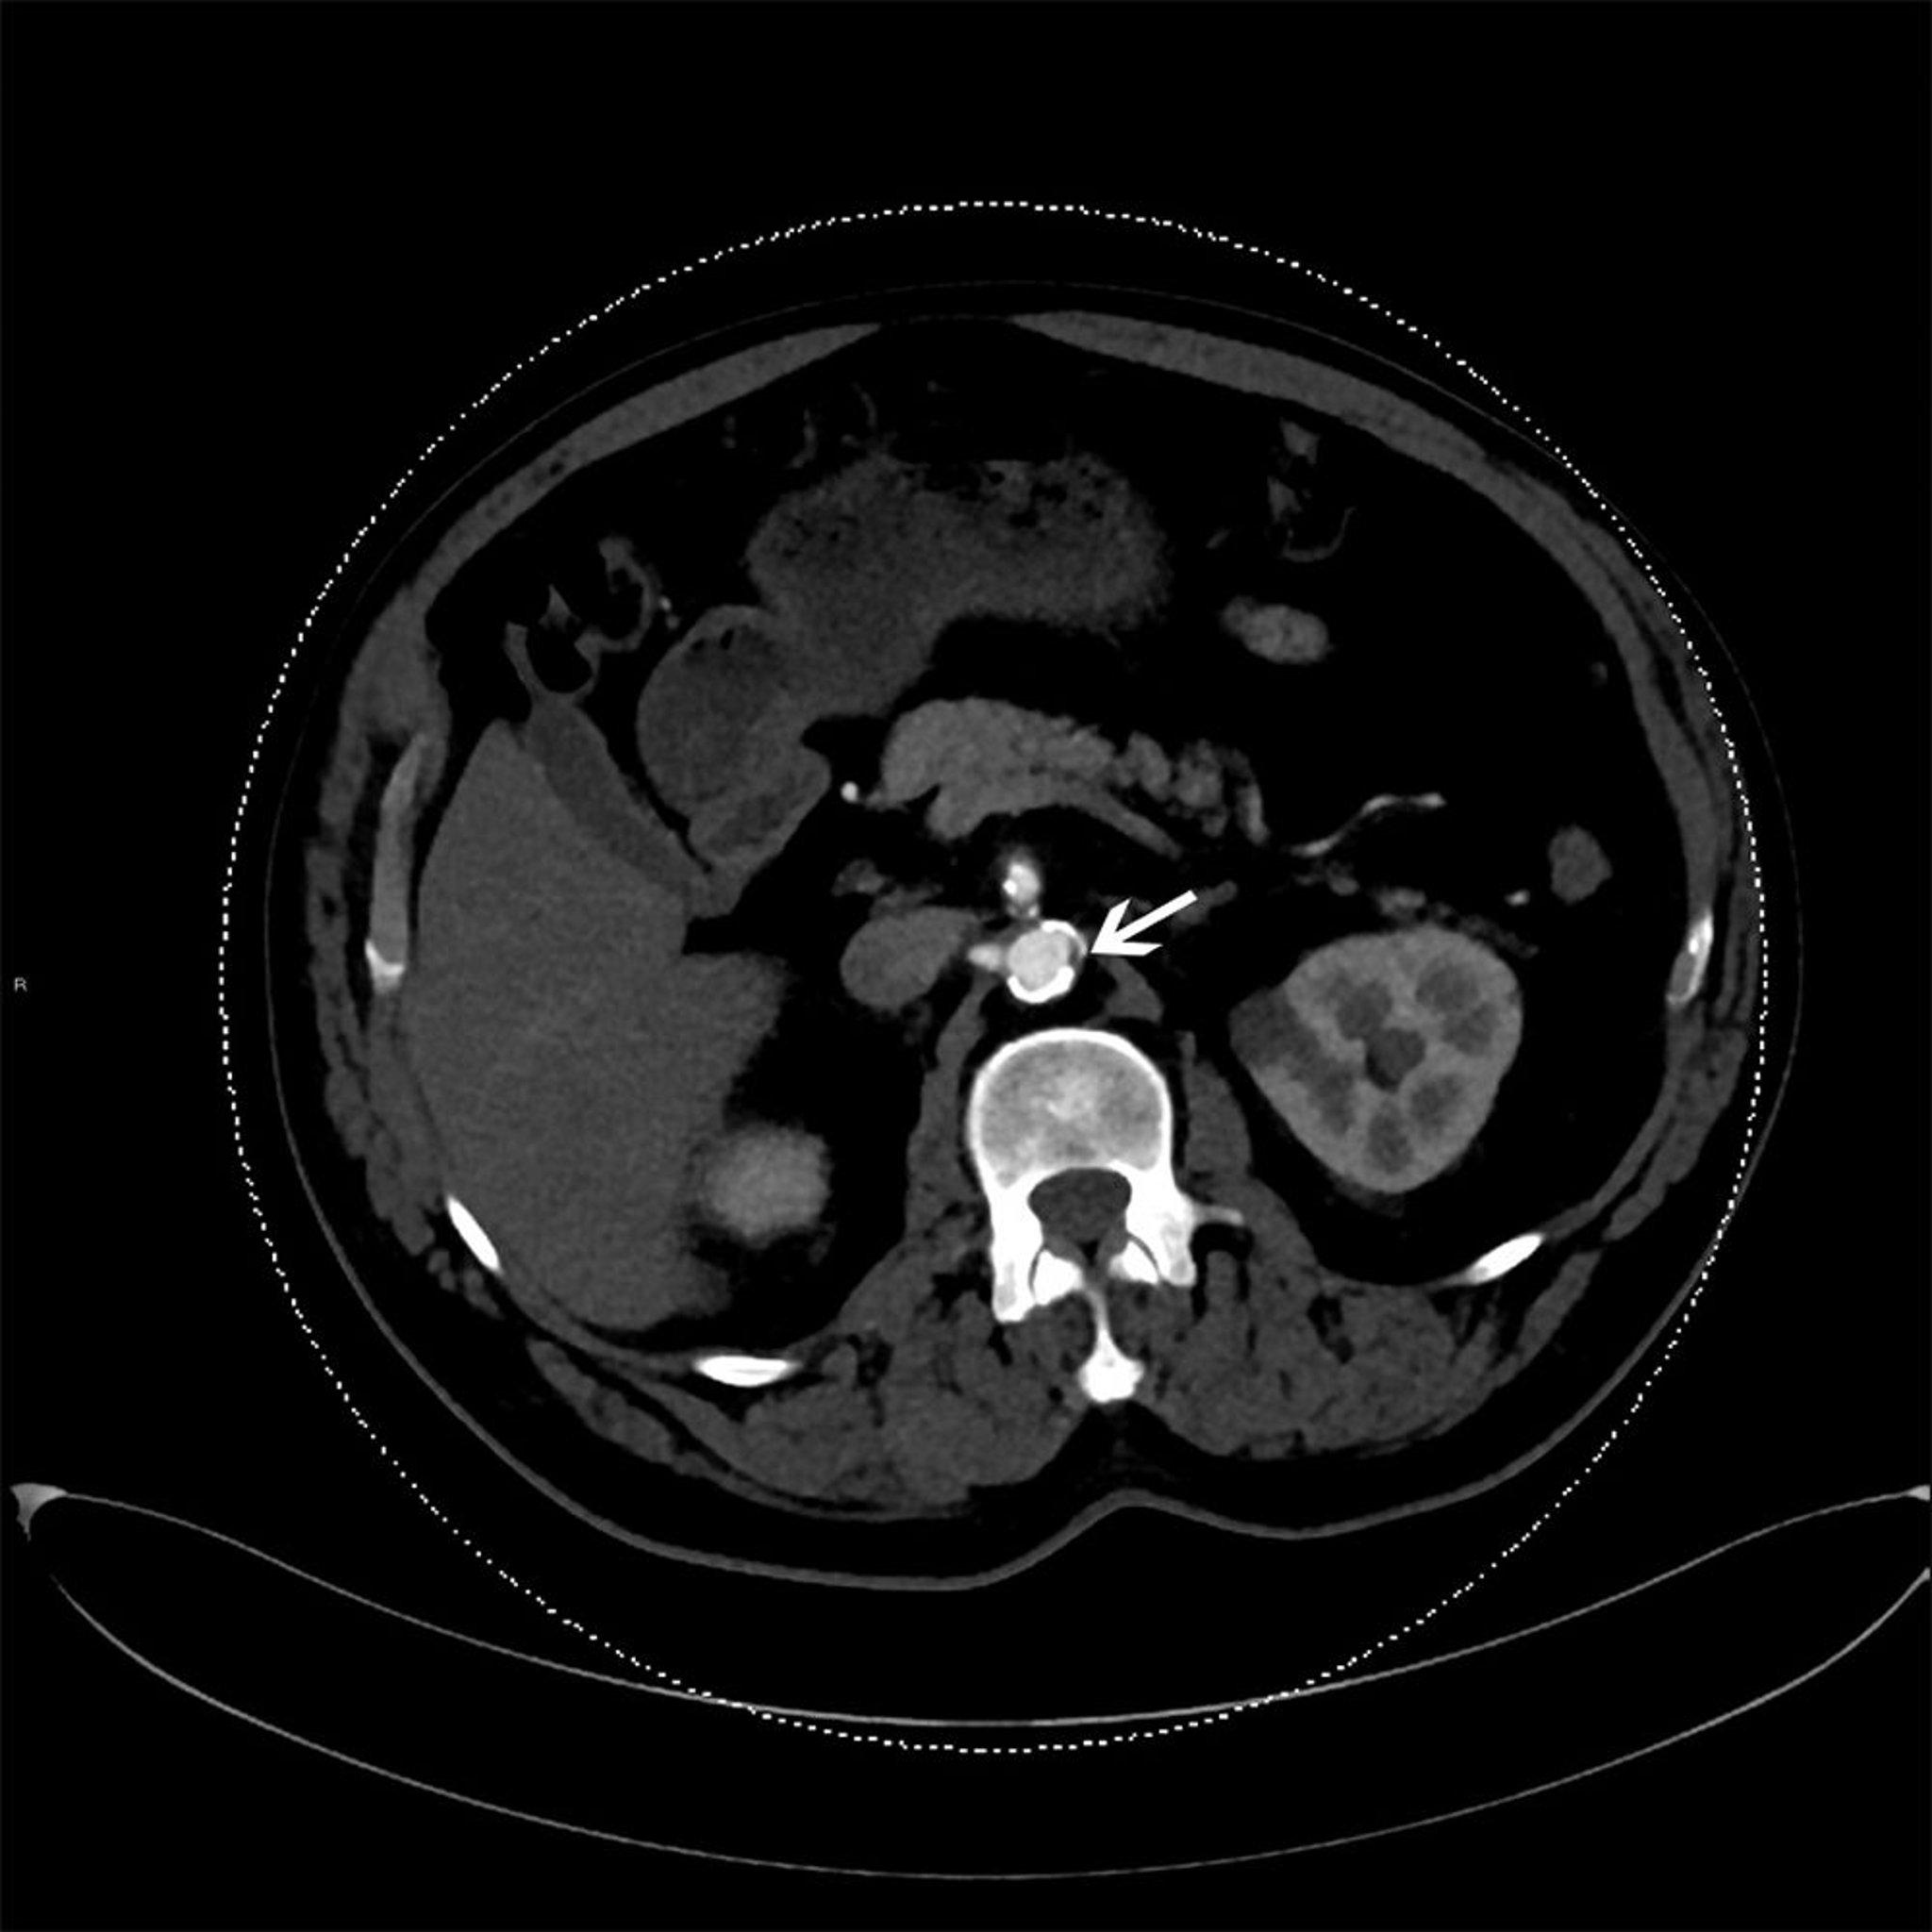

Questa scansione TC con contrasto mostra la placca aterosclerotica nell'aorta discendente (freccia).